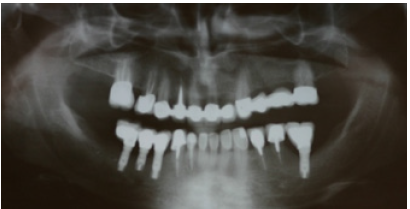

Figure 2: Preoperative panoramic radiograph.

The patient reported a free medical history, but admitted smoking habit (20+cig/day). He was not taking any medication and reported pain in facial muscles during stressful periods. The patient was subjected to thorough clinical and radiographic examination (panoramic x-ray) (Figure 2). Intraorally, he presented severe abrasion most observed in mandibulary dentition, reduced VDO, and several missing mandibular teeth (#44,45,46,47 and 36,37). In the maxilla, a 4-unit metal ceramic bridge with a cantilever was found on the incisors {12-11-21-(22)}, and one 4-unit metal-acrylic bridge in the posterior segment {23-(24)-(26)-27}. The visible diastemmas between #12,#13 and #13,#14 were due to a missing premolar #15 which probably caused distal migration of #14 and 13 (Figure 3-5). The smile line was evaluated as medium (Figure 6). Secondary caries was visible in amalgam restorations in #14 and #16 and was inspected under the abutment #12. A significant change in the occlusal plane was obvious, defined by significant protrusion of #13, #14 and #16. In the mandible acrylic crowns were positioned in #44, 33, 34. Initial radiographic examination revealed endodontic therapies in #12, 34, 35, 42 and #43 and it was estimated that the bone level averaged at 70%. Clinical examination of the stomatognathic system revealed bilateral myalgia of the lateral pterygoid muscles on palpation, unilateral clicking on the left TMJ and limitation in mouth opening. All other masseter muscles were free of symptoms.